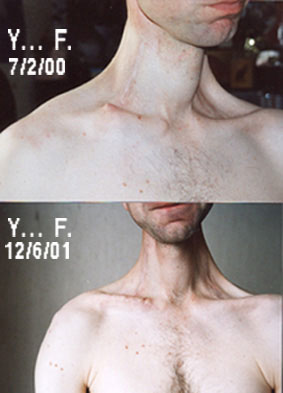

Image n° 3: Picture of both shoulders before and after surgery.

|

|

Clinical follow-up:

![]() November 2005. No pain, no rehabilitation problems. YF returned to sport. He teaches and plays tennis. He is again 15.

November 2005. No pain, no rehabilitation problems. YF returned to sport. He teaches and plays tennis. He is again 15.